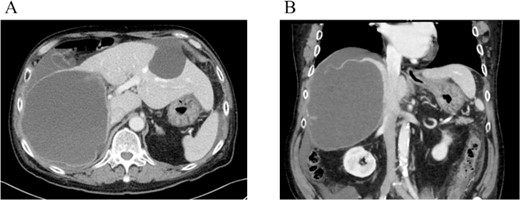

On referral to our hospital, his vital signs were within normal limits. The abdominal examination revealed rebound tenderness in his right upper quadrant region. There was no abdominal distension. The initial laboratory tests demonstrated a normal hemoglobin (10.2 g/dl) and elevated C-reactive protein levels (9.6 mg/dl). The results of serum tumor markers were as the follows: CA19-9, 193 784.3 U/ml; carbohydrate antigen 125 (CA125), 91.6 U/ml; carcinoembryonic antigen (CEA), 2.1 ng/ml; α-fetoprotein (AFP), 3.0 ng/ml; des-γ-carboxy prothrombin (DCP), 19 mAU/ml (Table 1). Dynamic CT showed a large cystic lesion (17 cm × 14 cm × 12 cm) in the right liver and discontinuation of the cystic wall and retention of ascites mainly the right subphrenic region (Fig. 1). T2-weighted single shot turbo spin echo magnetic resonance imaging (MRI) showed a-low intensity region with dorsal predominance in the high-intensity area and fluid–fluid level (Fig. 2). Gadoxetic acid (Gd-EOB) enhanced MRI didn’t show any lesion suggesting mural nodule in the cystic wall in any phase (Fig. 3). Paracentesis showed bloody fluid and the tumor marker levels in the sampled ascites were as the follows: CA19-9, 2 672 400.0 U/ml; CA125, 2618.9 U/ml; CEA, 41.7 ng/ml; AFP, 1.4 ng/ml; and DCP, 10 mAU/ml (Table 1). Cytology of the ascites showed no findings of malignancy.

Dynamic CT showed a large cystic lesion (17 cm × 14 cm × 12 cm) in right liver (A), and also the cystic wall rupture under the right diaphragm (B).